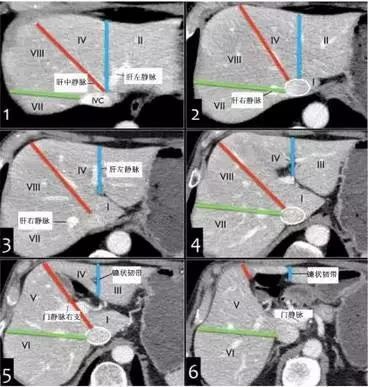

二、横断面解剖图示

(1)肝上部水平:由肝中静脉、肝右静脉、镰状韧带分段。

(2)门静脉左支水平:门静脉左支将肝分为上下部分,上方II和Iva,下方III和IVb。门静脉左支比右支位置高。

(3)门静脉右支水平:该水平门静脉右支将肝右叶分为上部(VII和VIII)和下部(V和VI)。

(4)脾静脉水平:脾静脉较门静脉右支低。可见III、IVb、V、VI段。

CT轴位分段

肝左右叶(IV段与V、VIII段)分界:沿胆囊窝上方肝中静脉至下腔静脉(下图红线)。

肝左叶(内侧II、III段与外侧IV段)分界:沿镰状韧带和肝左静脉、肝中静脉汇合处下腔静脉连线(下图蓝线)。

肝右叶(前侧V/VIII段与后侧VI/VII段)分界:沿下腔静脉下方肝右静脉至肝脏边缘(下图绿线)。